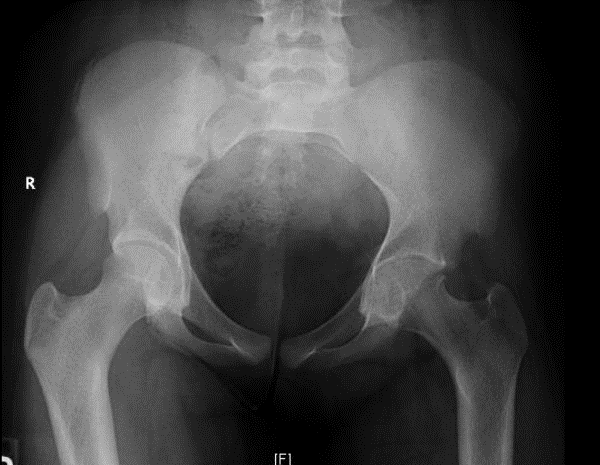

No diagnostic tests are available. X-rays show uniform joint space narrowing with a classic appearance. MRI has not been useful in evaluating the cartilage in these cases until advanced cartilage loss occurs.